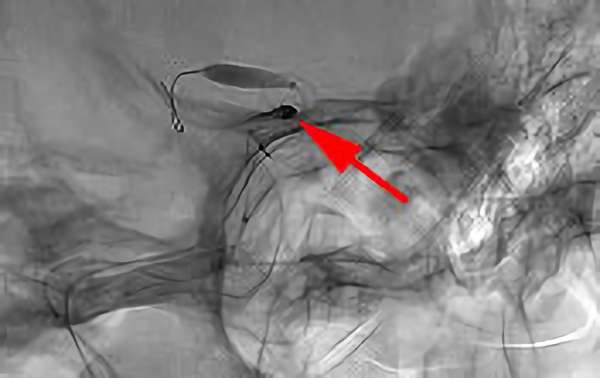

No.1631 手術中